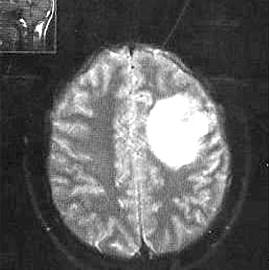

问题 小儿化脓性脑膜炎的临床特点是 ( )

选项 A.发热 B.头痛 C.呕吐 D.惊厥 E.脑膜刺激征阳性

答案 ABCDE